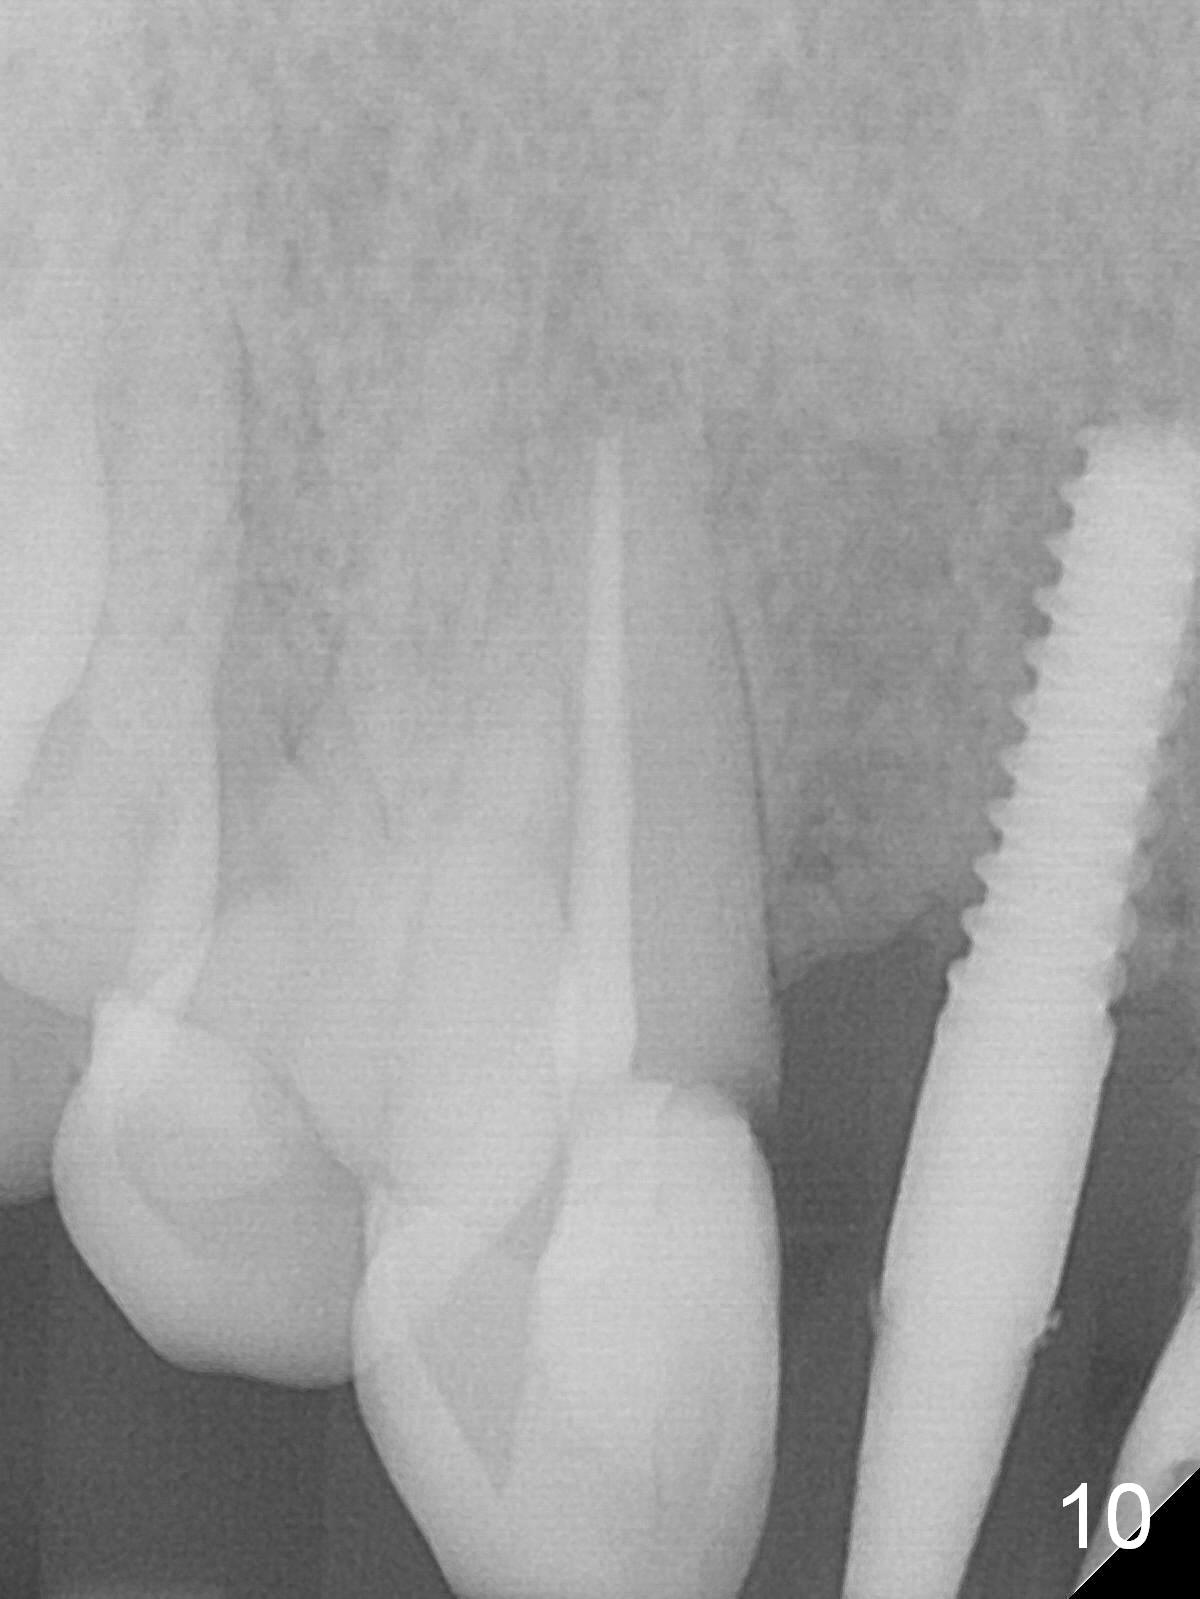

Preop exam shows the apparent wide ridge at #7 (Fig.1). What is ignored preop is the concavity in the apical buccal region (Fig.2 *). When a 3x16(4) mm 1-piece implant is being placed (Fig.3 *, flapless), the apical buccal plate vibration is felt. The biggest mistake is that initial osteotomy is ~ 6 mm shy of the implant length, partially because of 6 mm gingival height. Since the tooth #6 is symptomatic after RCT with paste overfill (Fig.4 >), apicoectomy is contemplated at #6 with exploration of the buccal plate at #7 (Fig.5). Since the implant appears to be long enough, implant apical resection is performed (Fig.6). Since there is coronal thread exposure due to previous periodontitis (Fig.7 <), bone graft is placed in these 3 defective areas after decortication.

Extending the initial osteotomy to the full length of the implant is critical. If perforation is detected early, the trajectory can be changed. Incision should be made if there is no CBCT study. The incision heals 1 and 4 weeks postop (Fig.8,9). The patient returns for final restoration 6 months postop. Apical defects appear to have healed at #6 and 7 (Fig.10,11). Fig.12 is taken 11 months postop and 5 months post cementation. The patient has an accident 9 months post cementation. In fact the implant is alright, while the tooth #6 fractures and #8 subluxates.